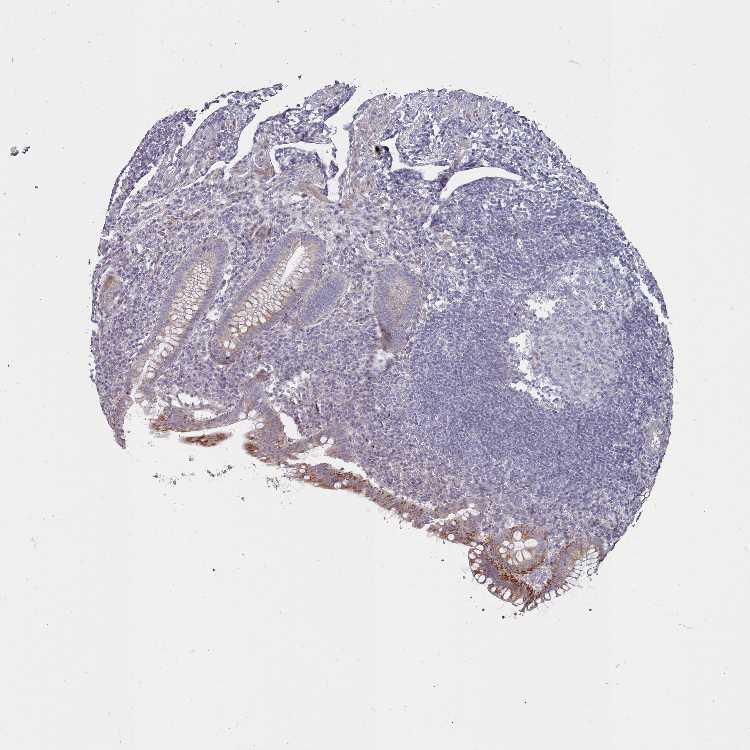

C3orf36